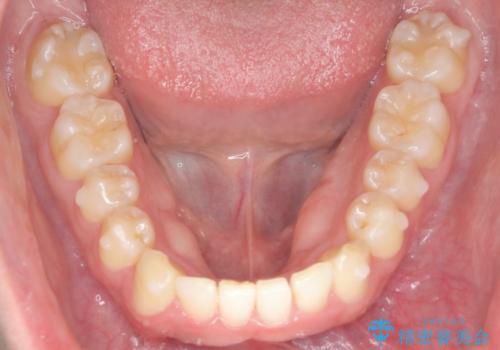

前歯が隠れていて見えない クロスバイトの矯正治療

- 「前歯が1本隠れていて見えない、歯並びを矯正治療で改善したい。」と希望され来院されました。

奥に隠れている前歯を並べられるスペースを確保したのち、歯並びを整えていきます。

前歯のスペース不足により1本だけ後方に位置している状態でしたが、しっかりとスペースを確保し配列することができました。